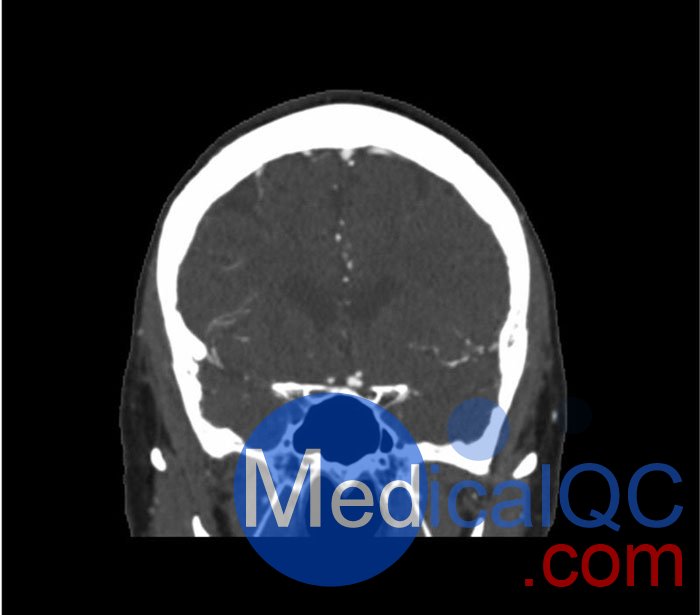

WEK50-03動脈瘤頭模,WEK50-03血管造影CTA頭模是頭部 CTA 動脈瘤模型

模擬造影劑動脈期頭部增強(qiáng)(CT血管造影)。 它覆蓋了頂點(diǎn)枕骨大孔。

模型有三個顱內(nèi)動脈瘤

大腦中動脈 (MCA) 的前部

交通動脈 (ACoA) 和基底動脈動脈。

WEK50-03動脈瘤頭模,WEK50-03血管造影CTA頭模影像圖:

更多效果和DICOM數(shù)據(jù)請聯(lián)系我們

SAG: